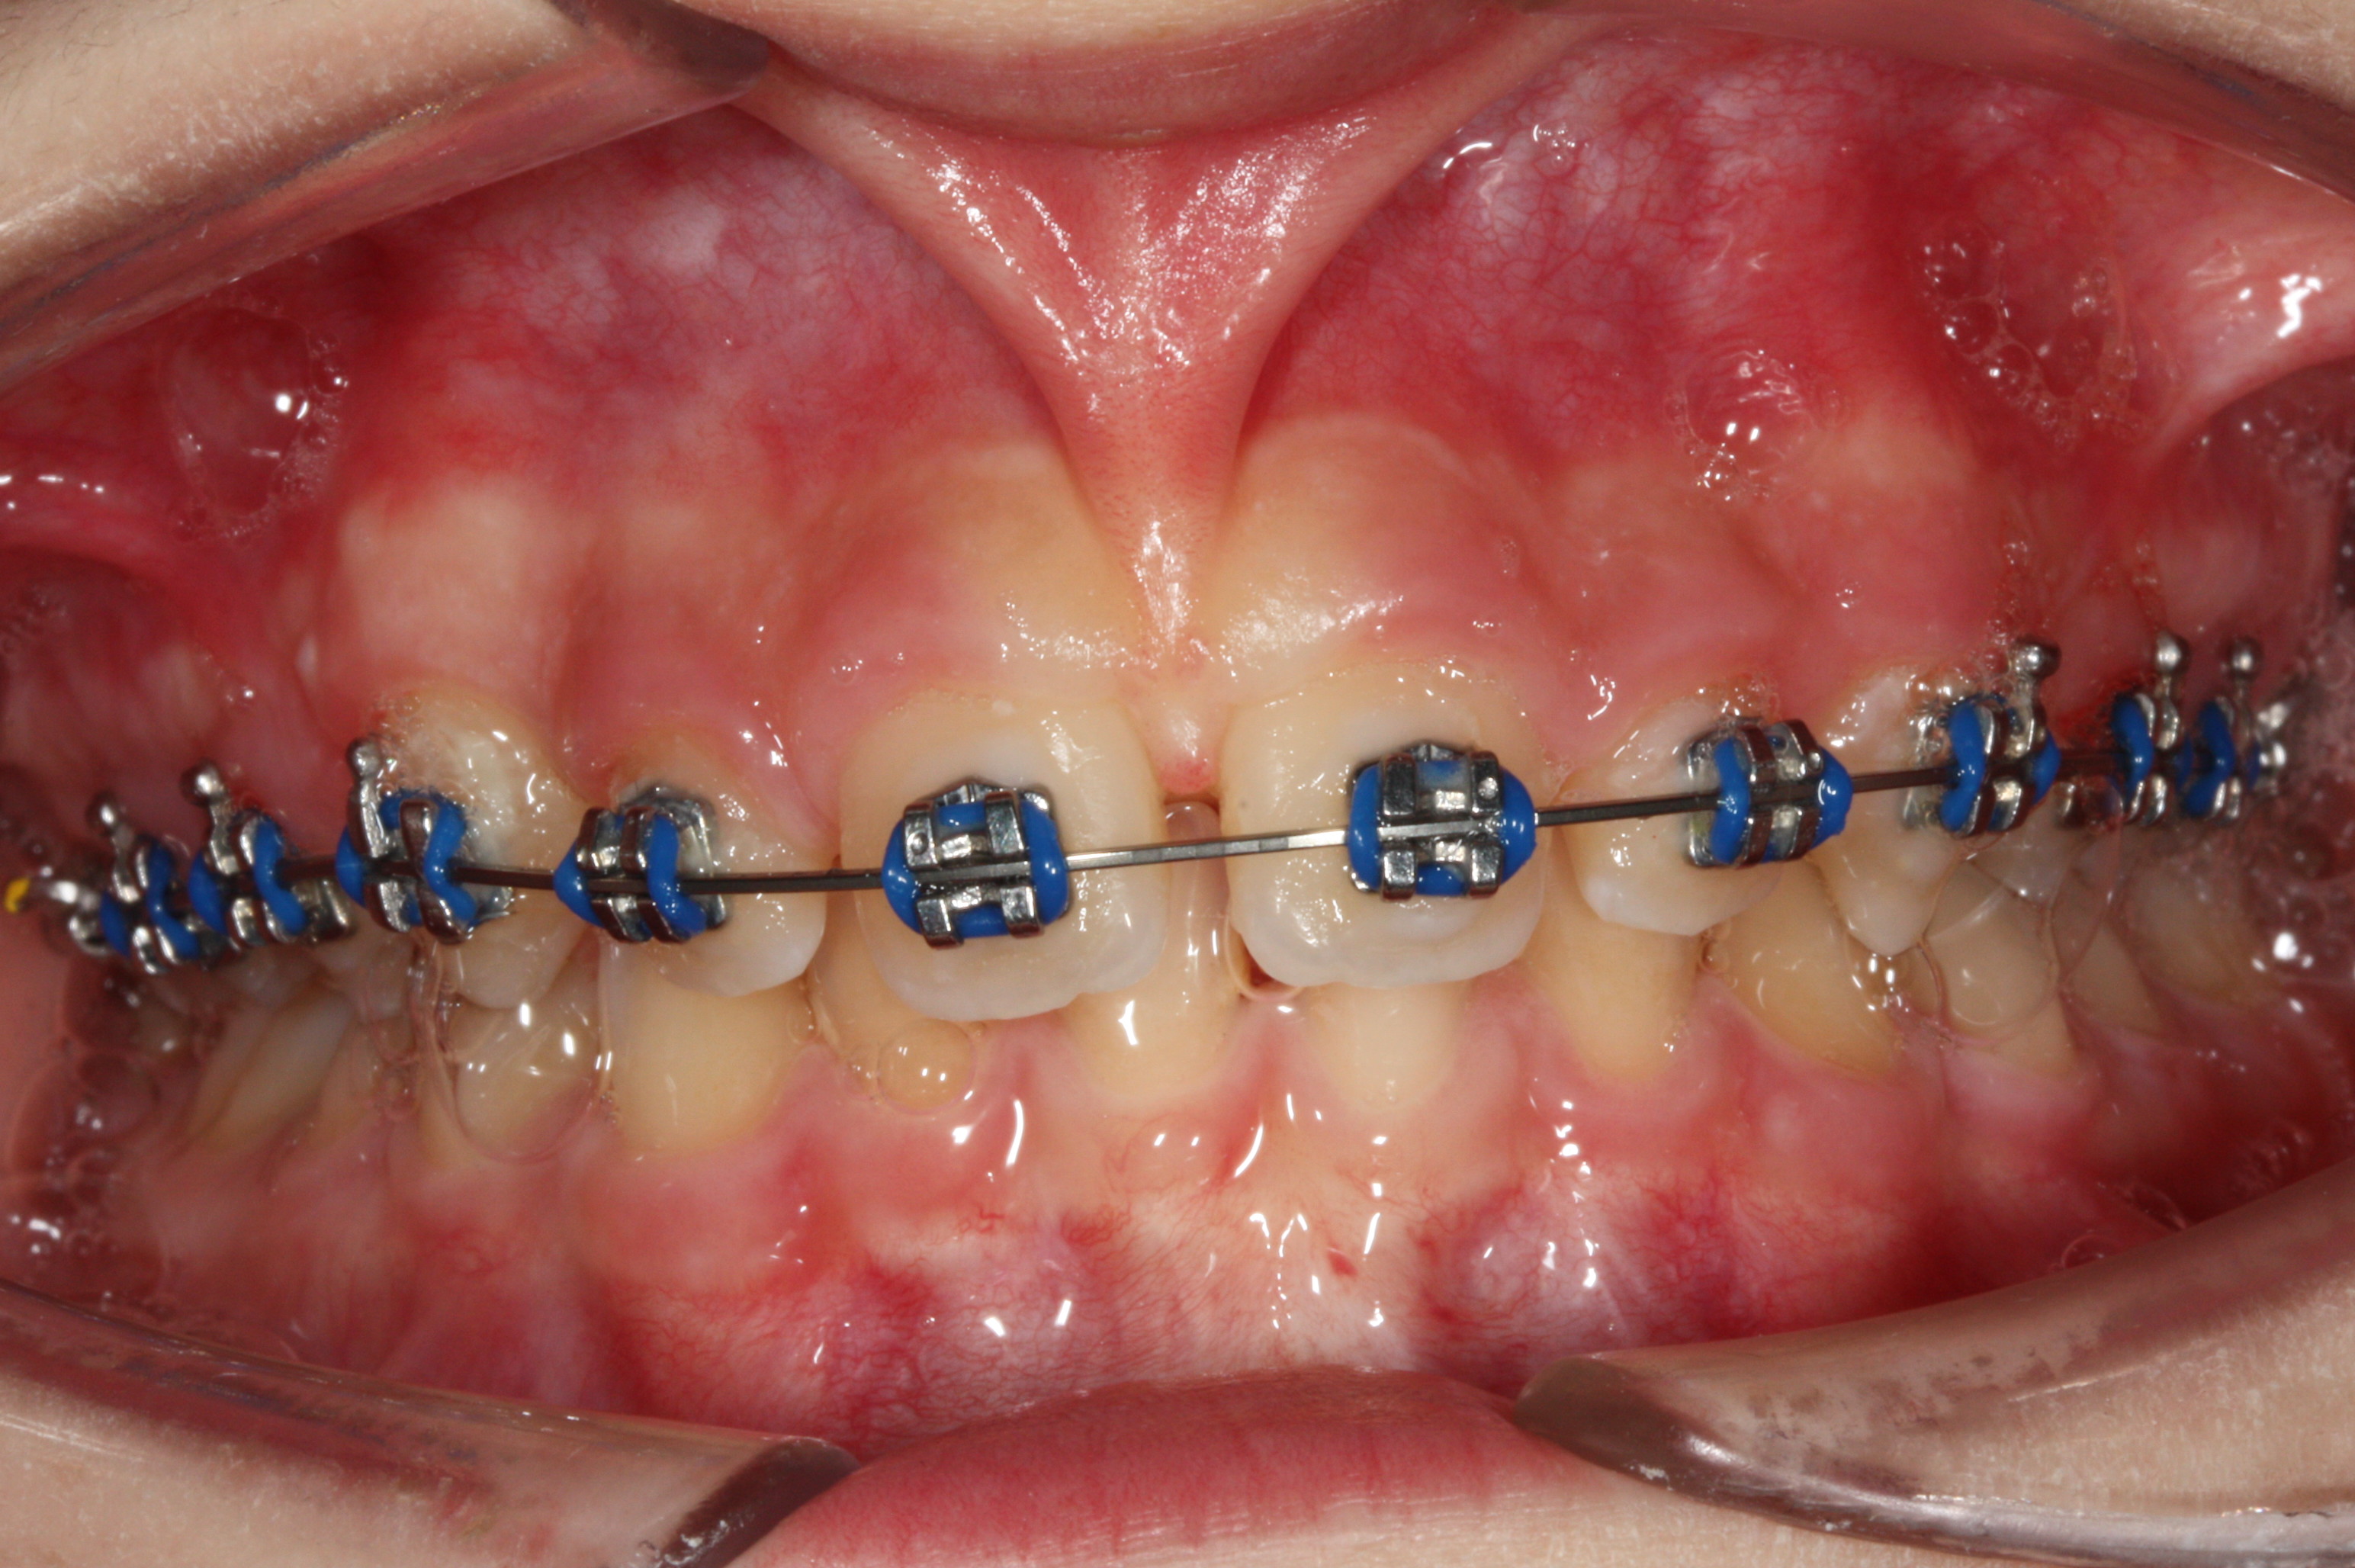

Frenulectomia eseguita in corso di trattamento ortodontico per esigenze estetiche del paziente.